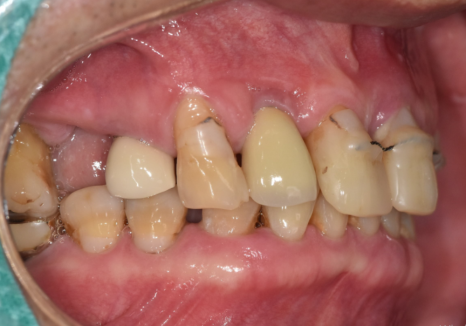

이번 환자분은 앞니가 많이 흔들렸습니다.

잇몸도 계속 부었다 가라앉았다를

반복하셨다고 합니다.

앞니가 너무 흔들리다 보니,

흔들리는 앞니 3개를

왼쪽 송곳니에 철사로

연결(스플린트) 해서 생활하고 계셨어요.

하지만, 방사선 사진과 입안을 살펴보니,

오른쪽 작은 어금니(#15) : 발치로 인해 치아 상실된 상태, 뼈가 다량 녹은 상태

앞니 3개 (#11,21,22) : 복합 치주염으로 뼈가 녹아 잇몸 상태가 좋지 않고 흔들림이 심함